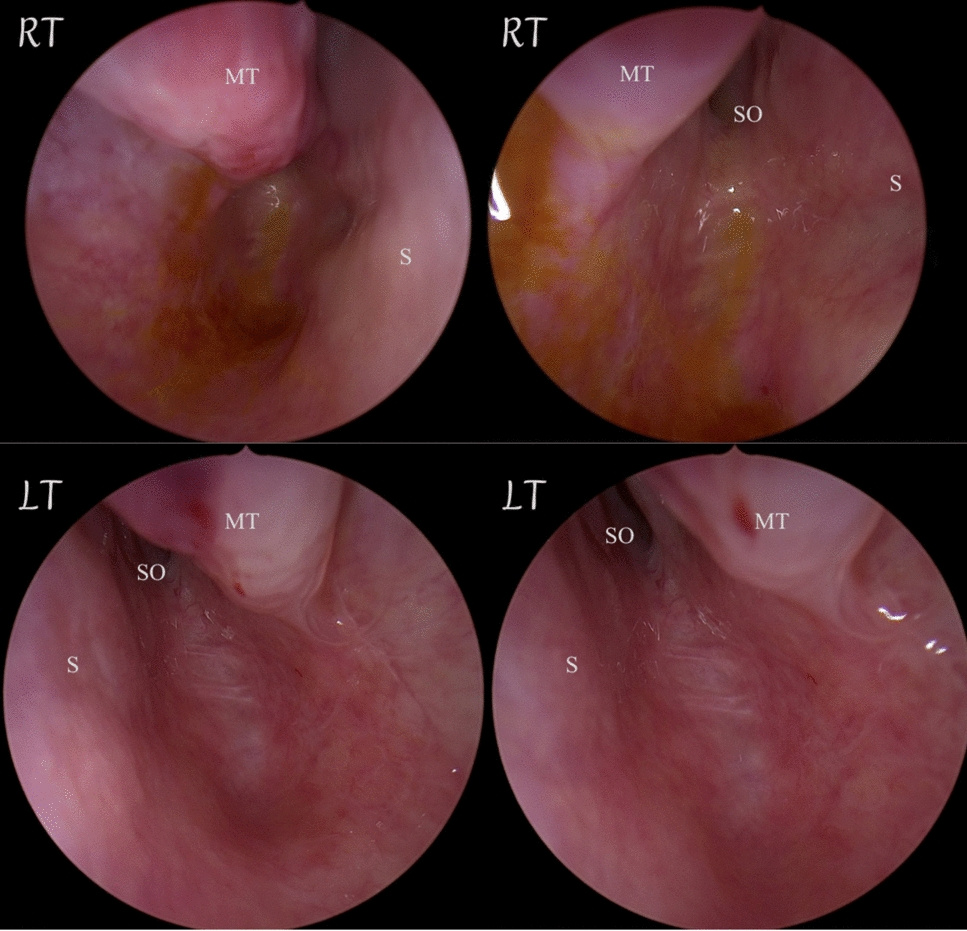

She denied any history of previous nasal trauma or nasal surgery. On examination, the patient has associated anomalies such as an arched palate, prognathism, disturbed alveolar arches, and mal occlusion class III. On endoscopic examination, the nasal septum was seen to be located at midline,

rudimentary middle turbinate, and bilateral posterior choanal plates were atretic . Computed Tomography (CT) showed Bilateral CA. Upon this, the patient was prepared for nasal surgery to open the posterior choana and establish the nasal passages.